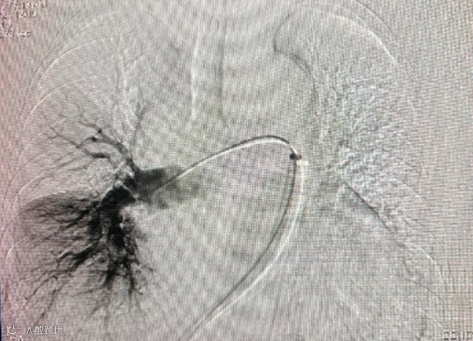

手术结束,将所有导管、鞘管撤出,穿刺点加压包扎。手术过程顺利,患者术后各监测指标平稳,安返病房。

术后造影